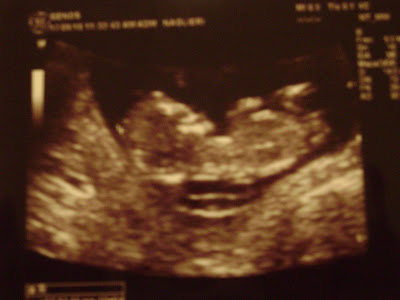

La princesa Sofia

Les presentamos a nuestro BEBE!

Sofi esta bien, hicimos todos los estudios... escuchamos su corazón que late muuuy fuerte y rápido, lloré de emoción con las ecografias, y Pepe nunca lo vi así, sin palabras mirando la pantalla como si fuese la cuarta parte de El señor de los Anillos en 3D. Emocionado, pero a su modo... del modo de los hombres que no lloran!

El momento de la eco se me pasa rapidísimo, me quedaría viendo y escuchando al bebé todo el día todos los días. En la semana subo la imagen para que la conozcan.